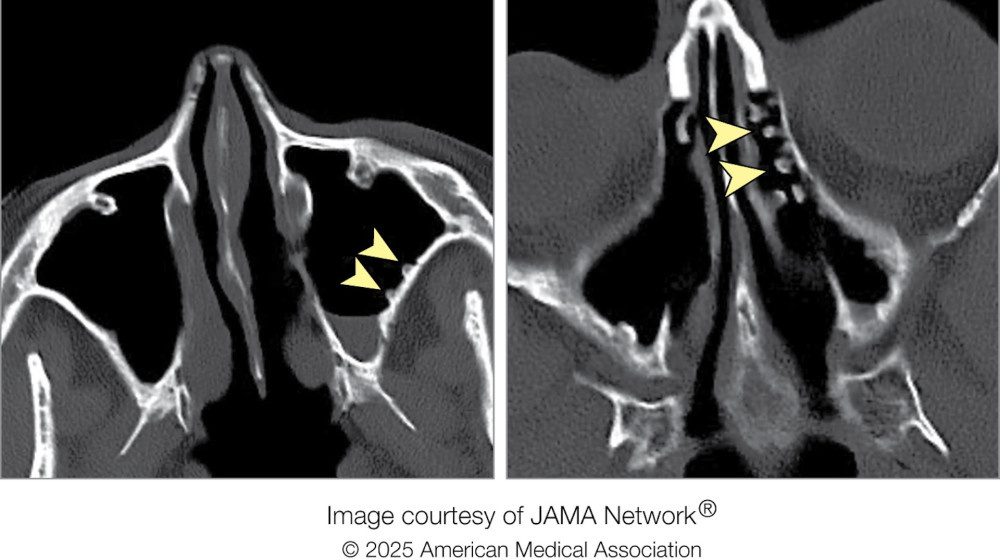

64-летняя жительница Миннеаполиса обратилась в клинику с жалобами на хронический риносинусит — воспаление слизистых оболочек носа и придаточных пазух. Ее мучили густые гнойные выделения, стекающие по задней стенке глотки, и постоянные головные боли. Однако врачи обнаружили нечто более необычное: под слоем слизи скрывались костные наросты, придавшие внутренней поверхности пазух вид булыжной мостовой.

Пациентка перенесла эндоскопическую операцию по поводу хронического синусита 23 года назад, но симптомы сохранялись. В течение восьми лет она использовала промывания с антибиотиками и физраствором, прекратив их за два года до визита. Когда врачи очистили пазухи от слизи, их ждал сюрприз: множественные костные выступы, напоминающие экзостозы — доброкачественные опухоли, обычно возникающие в ушных каналах у серферов из-за частого контакта с холодной водой.

"Это первый задокументированный случай, когда экзостозы сформировались в пазухах из-за длительных холодных промываний", — отметили авторы исследования.